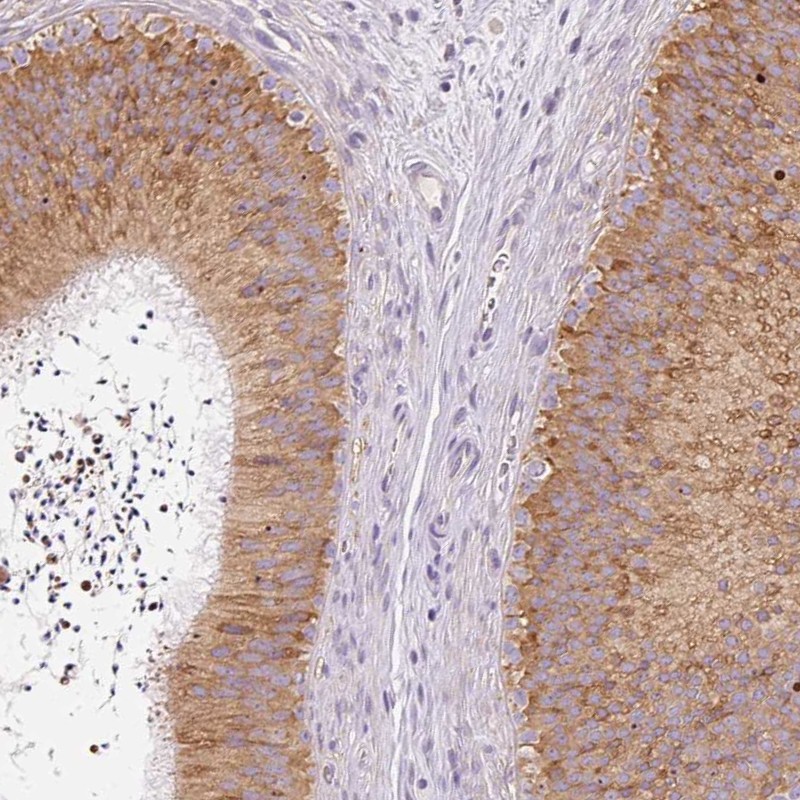

Immunohistochemical staining of human epididymis shows cytoplasmic positivity in glandular cells.